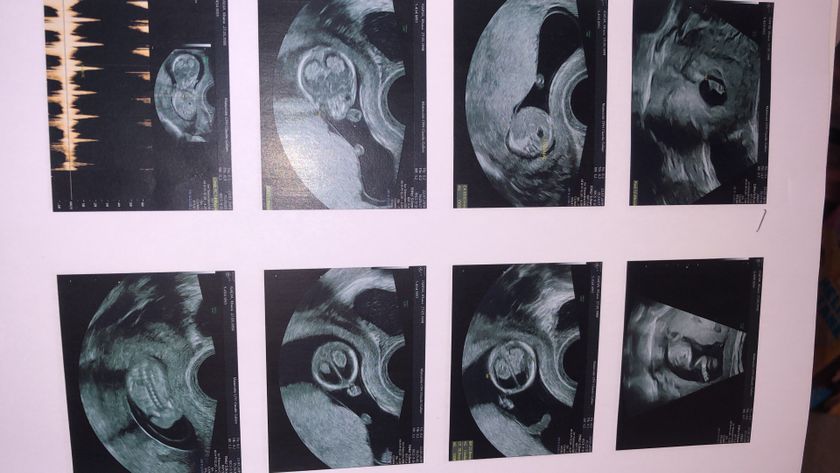

Была сегодня на первом Экографии, мой гинеколог который в 11 недель мне сказала что девочка,на простом Узи,не смогла посмотреть пол,Говорит не хочу ошибиться приди через месяц.я ей не верю,так как она была вся на нервах? кто разбирается в узи,есть тут что то?

на этом сроке сложно понять, мальчик или девочка в животике. разглядеть пол можно неделе на 15, и то есть вероятность ошибки